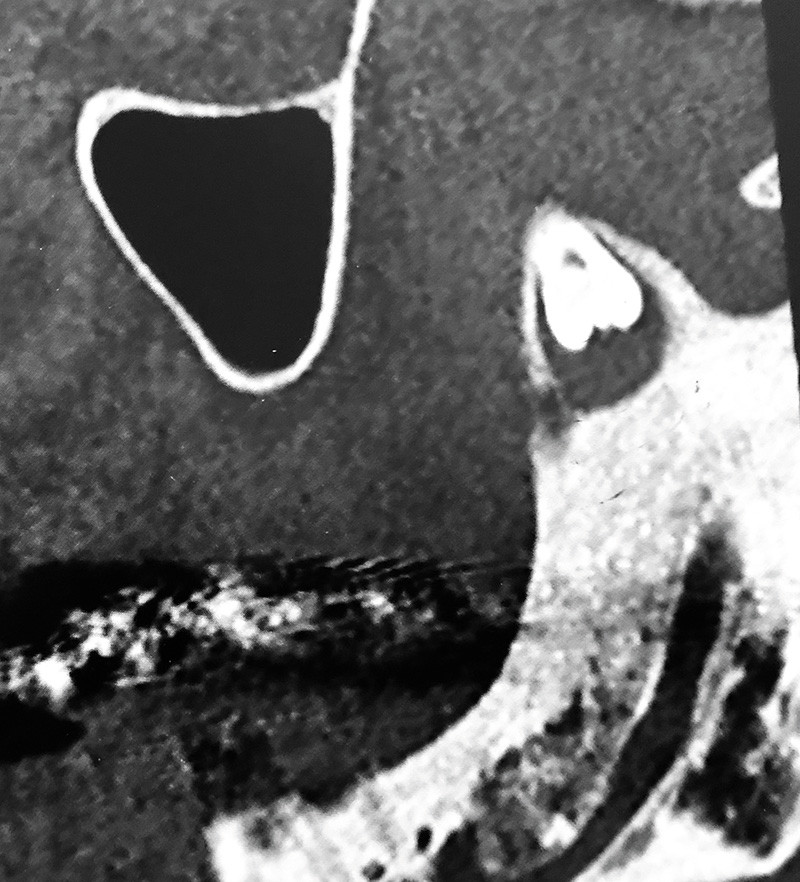

2. Du fait de la difficulté de diagnostic, un examen tomodensitométrique est réalisé (fig. 2). Quelles sont les propositions exactes ?

a. 28 incluse en position ectopique

b. 38 incluse en position ectopique dans le coroné

c. 38 dans la fosse infratemporale gauche

d. Lésion kystique mandibulaire gauche au niveau du coroné